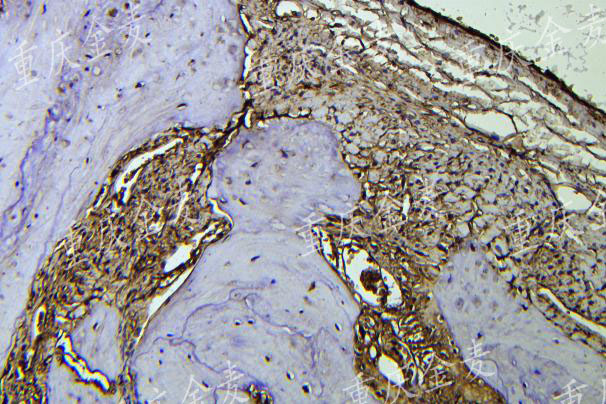

颅骨缺损材料修复OCN染色